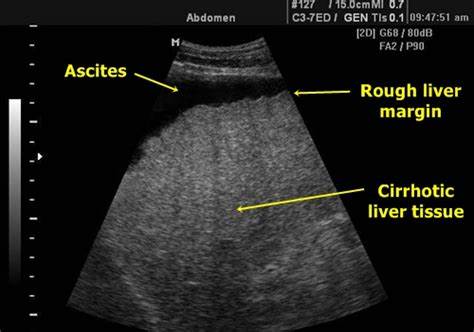

B超检查是肝硬化的常规检查。

上腹部的B超,是最常用的检查肝病的方法。目前所用的B超多数为彩色多普勒超声,也就是彩超。

- 晚期肝硬化的肝脏比较容易诊断,能看到肝内有大小不等结节的缩小的肝脏。

而有些肝硬化患者,可能合并脂肪肝或活动性的炎症,其B超可表现为:

- 肝脏表面结节和回声增强,伴有外观不规则的区域。

- 肝硬化的其他表现有:门静脉直径增加、门静脉血流减少、脾肿大、腹水、门静脉血栓形成等

超声检查,不能分辨早期肝硬化,所以有可能漏诊。

当有其他肝硬化证据的时候,需要结合临床表现进一步诊断。